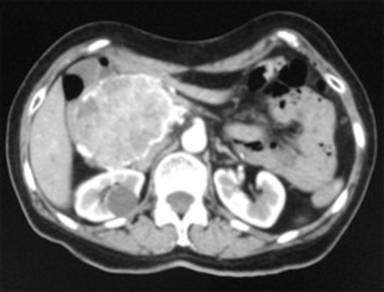

This is a case of a 52-year-old female who was admitted in our Hospital with abdominal pain and epigastric discomfort, findings on the physical examination were palpable mass on right hypocondrium and mild tenderness. She did not have history of other comorbidities. The Ultrasonography and CT scan findings were: a well-circumscribed tumor arising from the right hepatic lobe, diameter of 90mm, compressing other abdominal structures, suggesting as a possible diagnostic and hepatic hemangioma (Figure 1). Initial management was CT-guided angioembolization (two sessions). After this management, she presented a mild relief of the symptoms. A new CT scan revealed a mild reduction on tumor´s size; location of the lesion suggested a tumor arising of the head of the pancreas with clear borders, attenuation values of 18-27 Hounsfield units, heterogeneous enhancement and vascularity present within, the adjacent organs were compressed, and no enlarged lymph nodes were found (Figure 2). Laboratory tests, tumor markers (CEA and CA19-9) and gastric endoscopy were normal. Endoscopic ultrasound was not available in our institution. At this scenario, lacking of biopsy, high suspicious of malignancy, the patient´s symptoms and because the tumor´s size, we decided to perform a pylorus preserving pancreaticoduodenectomy; there was a total bleeding of 400ml and surgical time of 5 hours. It was no need for ICU admission and transfusions. No surgical complications were reported. Before discharge of our service, patient presented seizures secondary to arteriovenous malformation in frontal lobe found in brain CT and MRI; she had no previous history of neurologic symptoms. Diagnostic and therapeutic protocol was in charge of Neurology and Neurosurgery department, but she died one month after the surgery. Histopathological findings were: hemolymphangioma of pancreatic head; with a size of 8x6.5x6 cm; solid component with focal mucinous cysts. No invasion to others structures were reported. Peripancreatic lymph nodes were normal (Figure 3).

Figure 2. CT scan control demonstrating a mild shrink of tumor’s size and location at pancreatic head. |